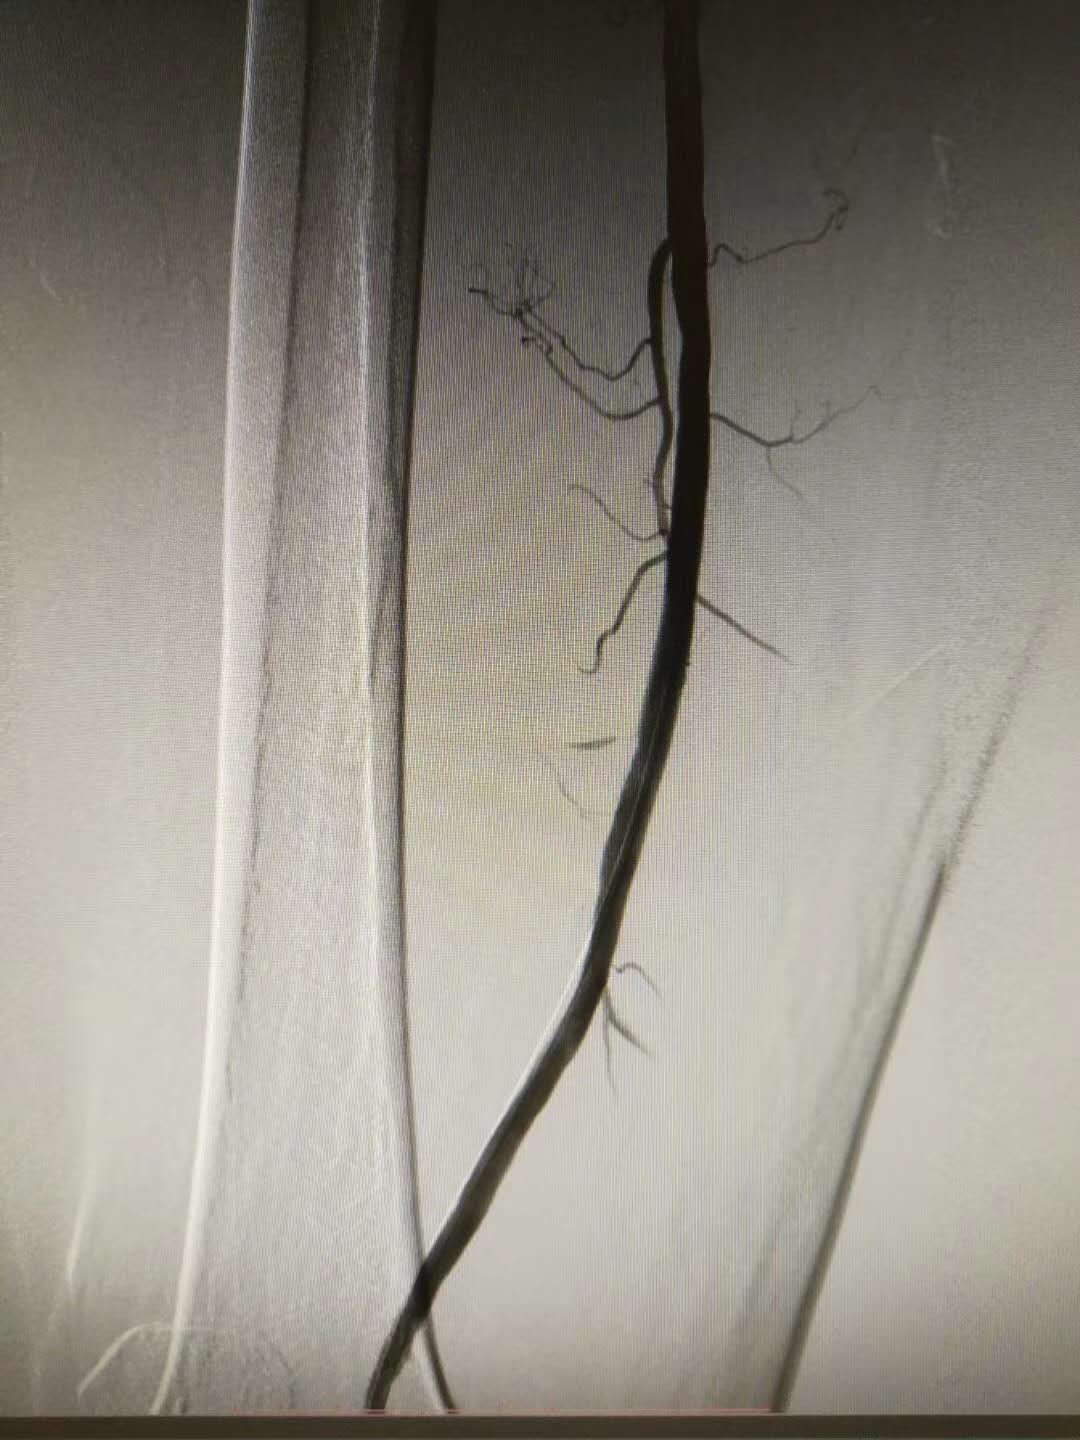

最后复查造影,提示股浅动脉远端管腔通畅,血流速度满意,未见动脉夹层形成,侧枝循环显影较前减少,手术成功。术后患者自述“走走停停”的症状较前明显改善,生活质量得到改善。

注:图中黑影代表在注射造影剂后血管显影情况。